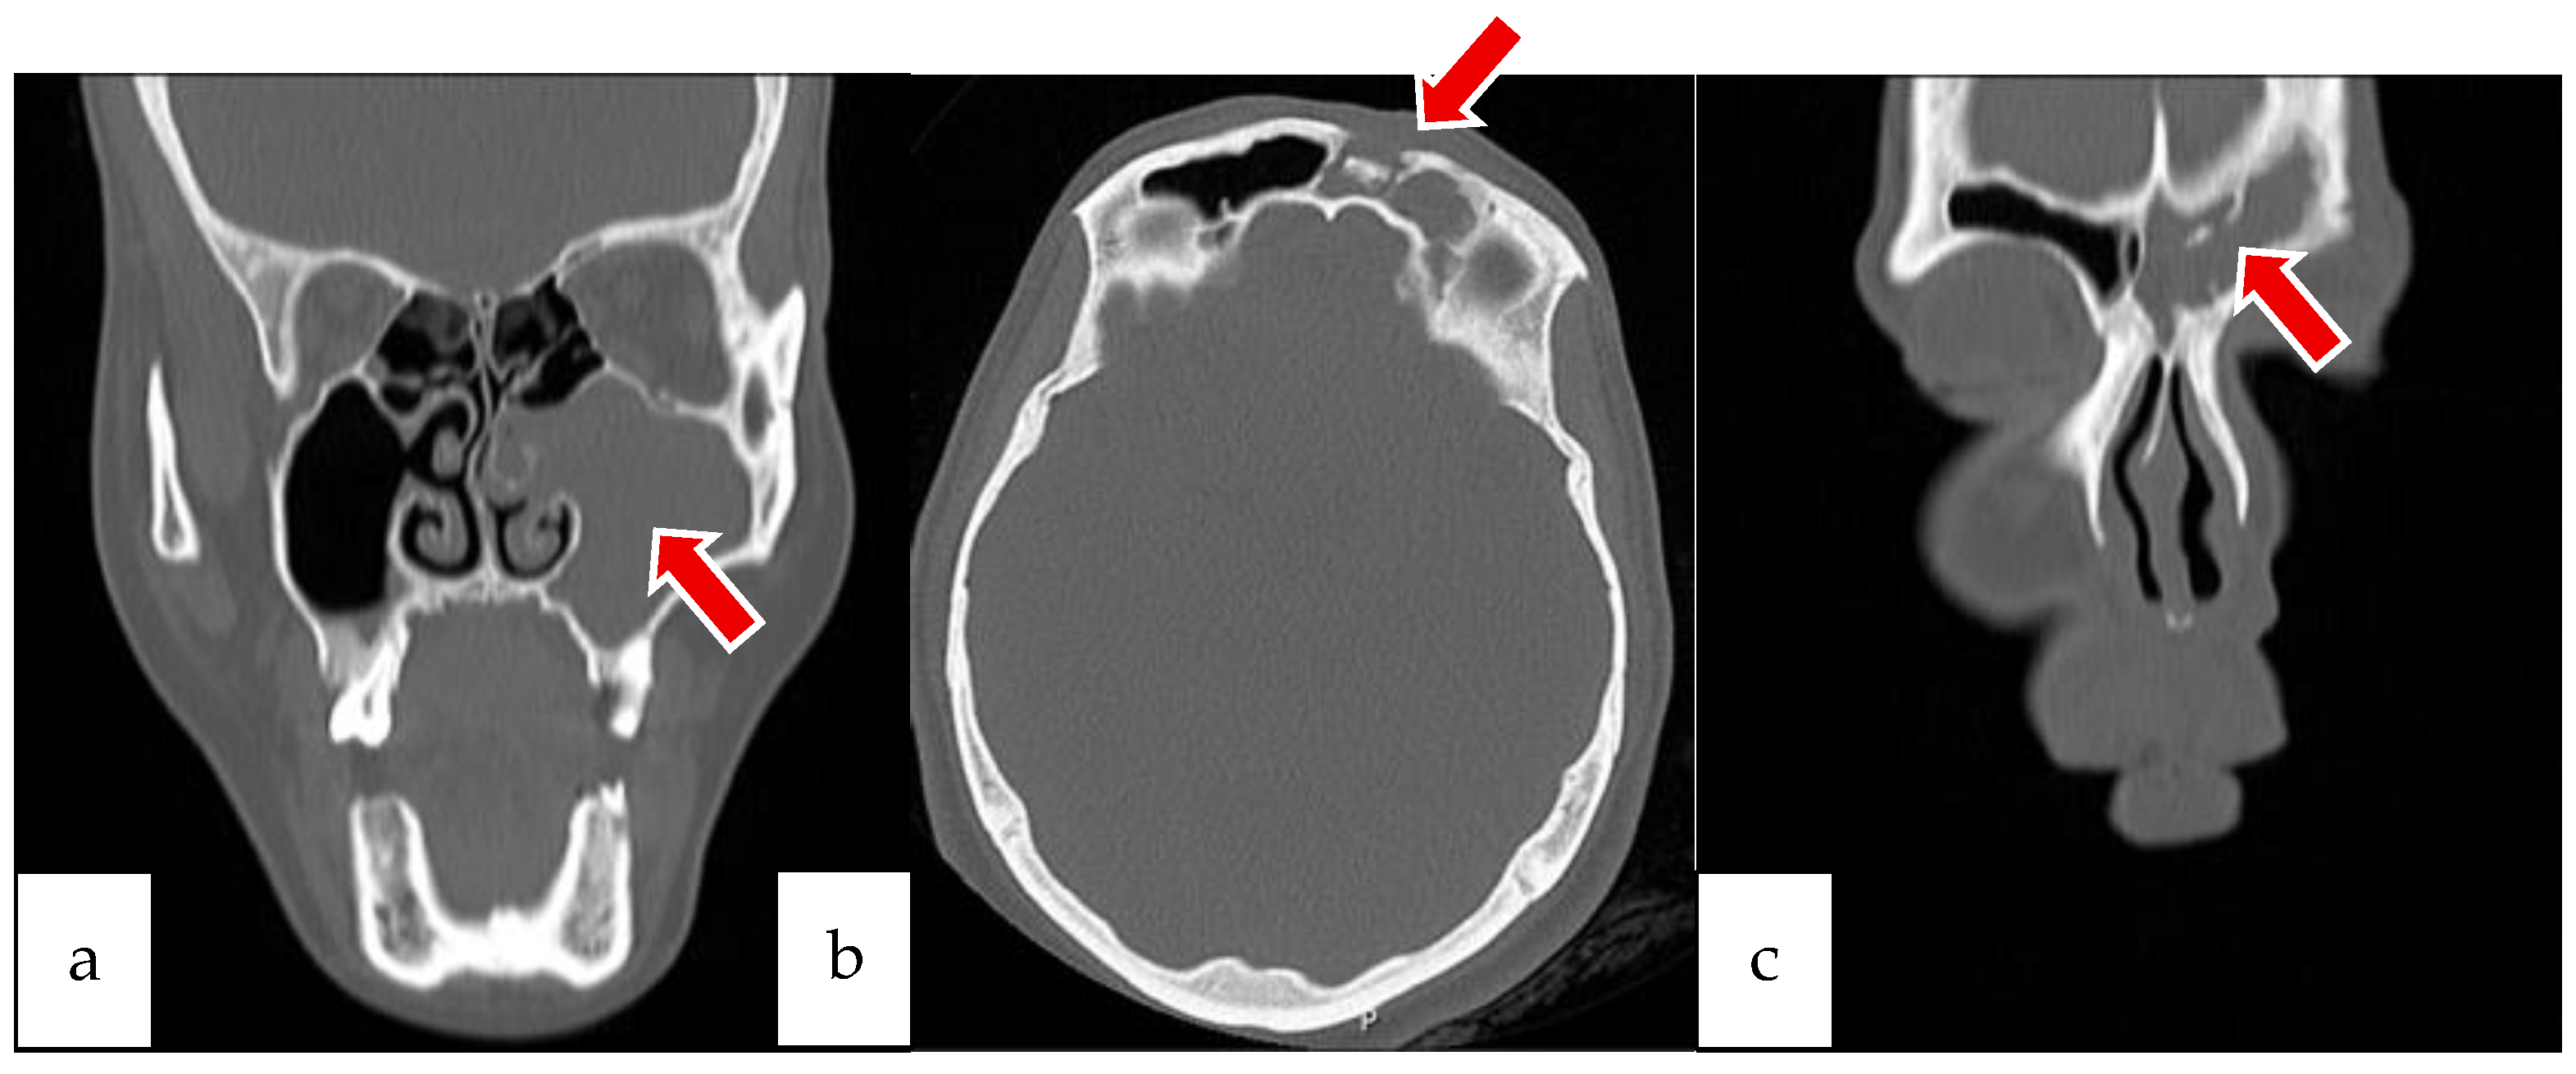

2.1. Case 1